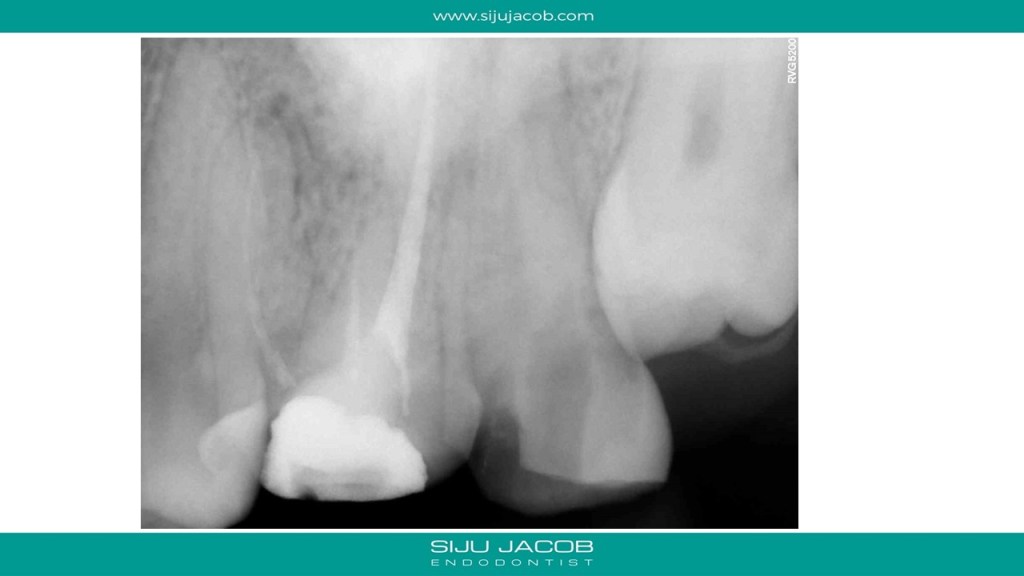

Some cases are such that when you eventually finish, you wonder what the fuss was all about. I struggled to locate the canals in this case. Not sure why. Yes, the access was difficult, but the main reason I struggled was probably the prior access that was made. This made me lose orientation initially. I managed to locate one canal and then took an Inter-appointment CBCT. This made things much easier. More in the short video below:

And below are the clinical slides of the same case: